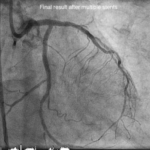

Impella Protected Rotablation PCI

A high-risk PCI performed with Impella support and rotablation for optimal safety and outcomes.